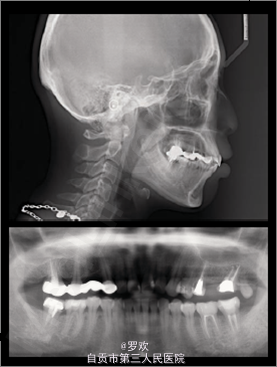

闭唇时颏肌紧张,露龈笑,凸面型 A4A6B6 缺失,A3-A7,B5-7 局部固定桥修复 II类关系(右侧) ,下中线右偏2mm 侧位片:高角,凸面型,唇前突, SNA82°,SNB78°,ANB4°, 全景:多个牙缺失